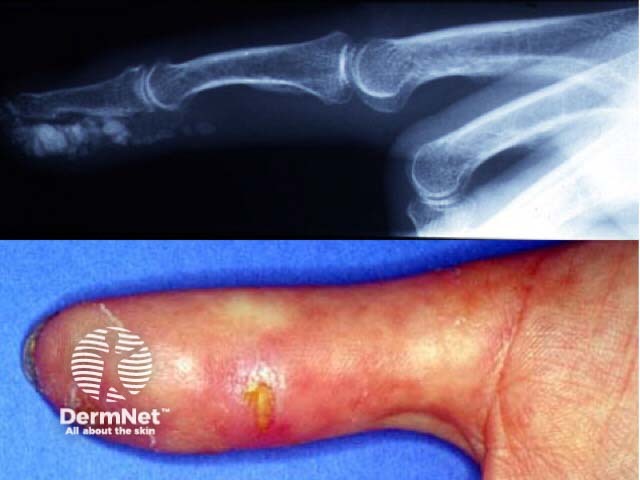

Calcinosis cutis

Digital ischaemia in systemic sclerosis